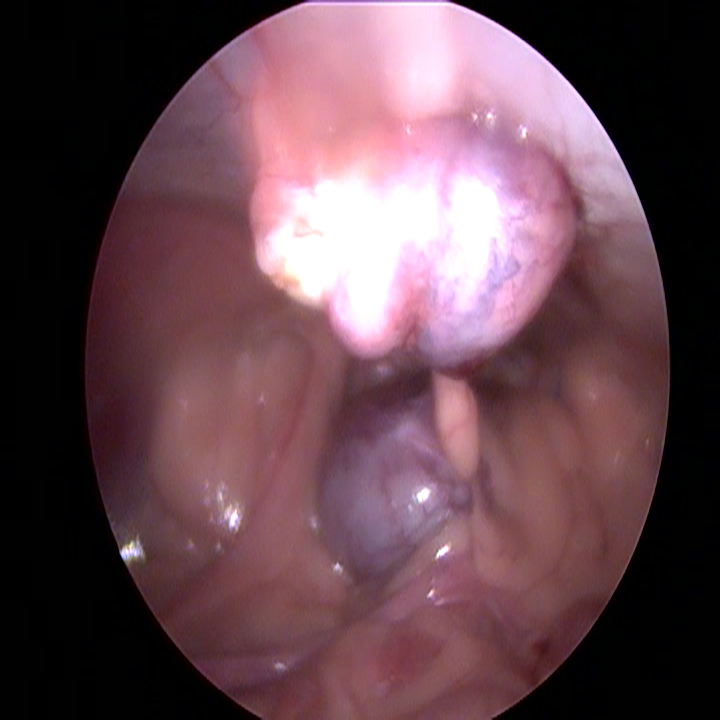

Wanneer alle trocars geplaatst zijn, kantelen we de operatietafel naar voren en leggen we de patiënt op haar zij. Dan gaan we op zoek naar de linker eierstok. Doordat de milt eroverheen ligt kan dit soms wat meer moeite kosten. Eenmaal gevonden, branden we de ophangbanden en bloedvaten van het ovarium door. Hierbij moet ervoor gezorgd worden dat er ver genoeg van de nieren en de buikwand af gewerkt wordt, om hitteschade te voorkomen. De eierstok wordt via het gat bij het bekken verwijderd. Na het controleren van de plek waar de eierstok verwijderd is en na het opnieuw plaatsten van de achterste trocar, wordt de andere kant gedaan.

De hond wordt hiervoor naar de andere kant gekanteld. De darmen moeten worden weggemasseerd en wanneer de eierstok gevonden is, herhaalt de procedure zich.